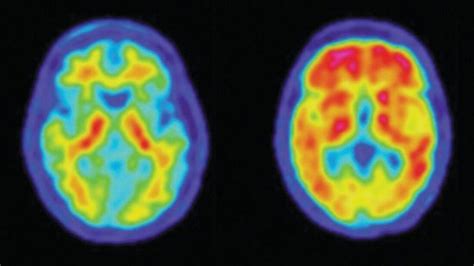

Now, you might be wondering, “Why is looking at function so important?” Great question, guys! The real power of PET scans lies in their ability to detect diseases at their earliest stages and to provide crucial information for treatment planning and monitoring. For instance, in oncology (cancer care), PET scans are a game-changer. They can help doctors differentiate between cancerous and non-cancerous tumors, detect if cancer has spread to other parts of the body (metastasis), and assess how well a tumor is responding to treatment. Imagine a patient undergoing chemotherapy. A PET scan can show if the cancer is shrinking or becoming less active before structural changes are visible on other imaging tests. This allows for timely adjustments to the treatment plan if it’s not working effectively. Beyond cancer, PET scans are invaluable for diagnosing and managing neurological disorders. They can help identify changes in brain activity associated with Alzheimer’s disease, Parkinson’s disease, epilepsy, and other brain conditions. For example, in Alzheimer’s, PET scans can reveal patterns of reduced metabolic activity in specific brain regions, offering a clearer picture of the disease’s progression. They’re also used in cardiology to assess blood flow to the heart muscle, helping to diagnose coronary artery disease and determine the extent of damage after a heart attack. In essence, PET scans provide a unique window into the body’s internal processes, offering insights that other imaging techniques simply can’t. This detailed functional information empowers healthcare professionals to make more accurate diagnoses, personalize treatments, and ultimately improve patient outcomes. It’s this ability to see the unseen, the subtle changes happening at a cellular level, that makes PET scans an indispensable tool in modern medicine. They are truly at the forefront of diagnostic imaging, pushing the boundaries of what we can see and understand about human health.